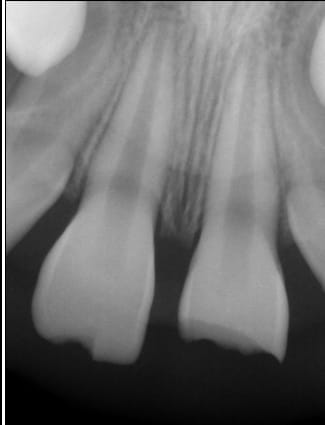

J ai eu une petite au cab qui vient suite a une chute .

fracture de la 11 et 21 il y a 2/3 srmaines..

test au froid ok sur la 21 . la percussion n est pas douloureuse, pas de mobilité et je n entend pas de son particulier.

La patiente ne se plaint pas de douleur

Surveille bien car une plaie laissée 2/3 semaines ouverte, c'est limite en terme de risque d'atteinte pulpaire.